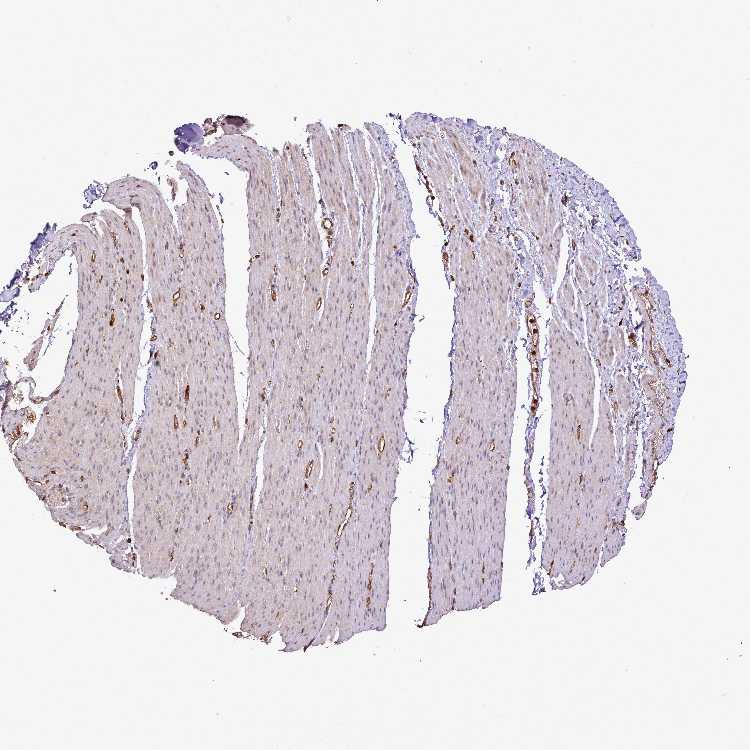

ADIPOSE TISSUE - Antibody stainingi

Antibody staining in the annotated cell types in the current human tissue is reported as not detected, low, medium, or high, based on conventional immunohistochemistry profiling in selected tissues. This score is based on the combination of the staining intensity and fraction of stained cells.

Each image is clickable and will lead to virtual microscopy that enables deeper exploration of all samples and also displays staining intensity scores, fraction scores and subcellular localization as well as patient and tissue information for each sample.

Antibody CAB045963

Adipocytes Medium